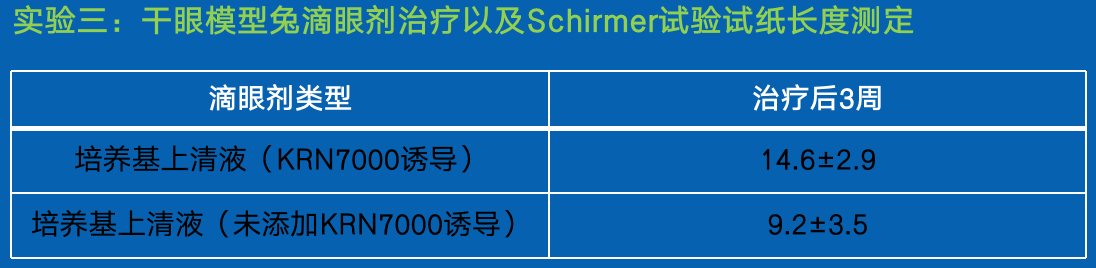

结论:

采用制备的滴眼剂进行一段时间的治疗后,白兔

的干眼症症状均有所缓解,其中,添加 KRN 7000 诱导的培养基上清制备的滴眼剂,恢复效果明显优于未添加 KRN 7000 的培养基上清制备的滴眼剂。